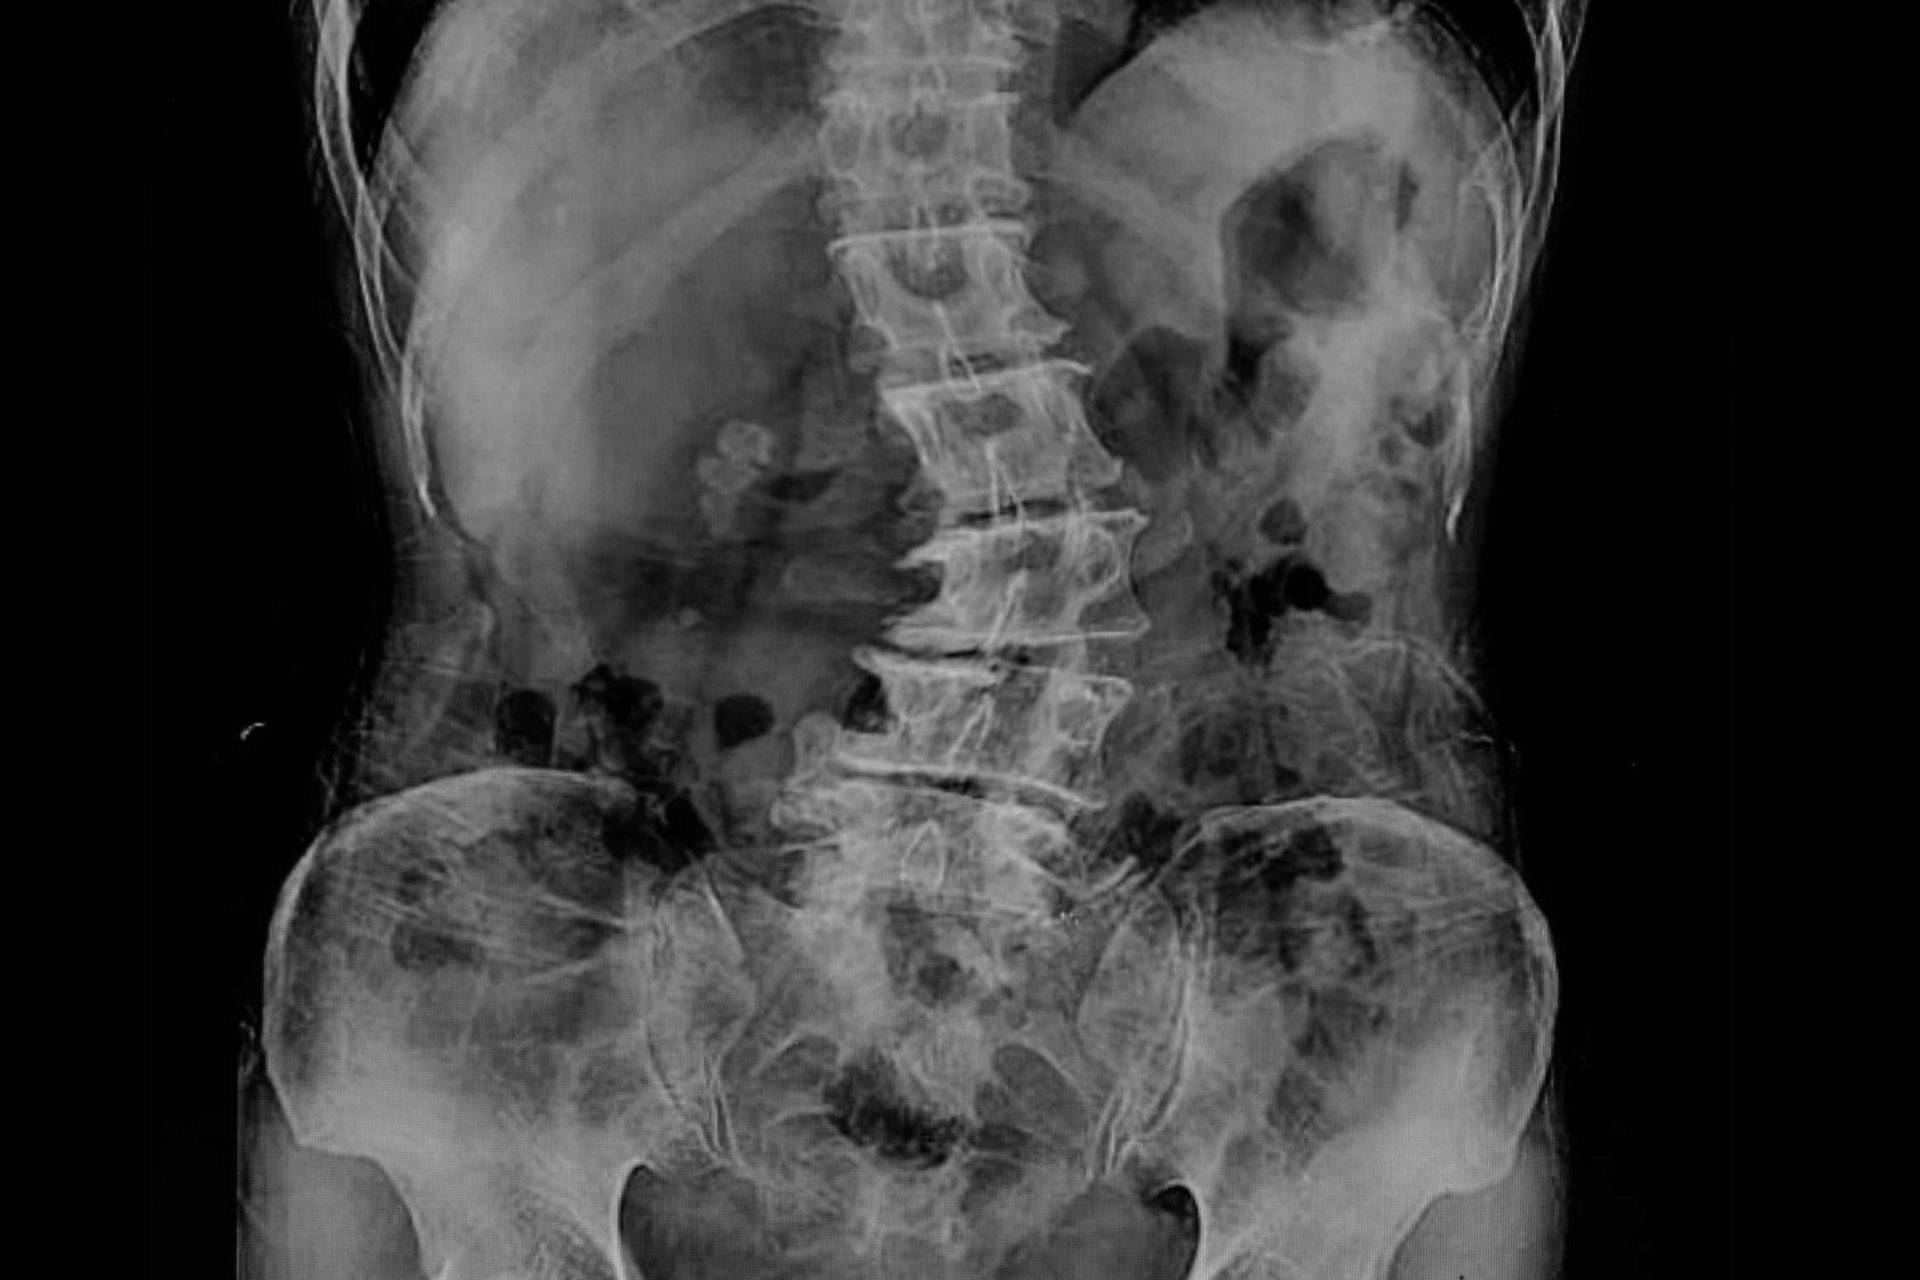

Para diagnosticar la escoliosis lumbar, los profesionales de la unidad médica Biziondo pueden llevar a cabo un examen físico, una radiografía de la columna vertebral o una resonancia magnética. En ese sentido, lo ideal es obtener un diagnóstico temprano mediante un examen médico, con la finalidad de prevenir la aparición de complicaciones a largo plazo.